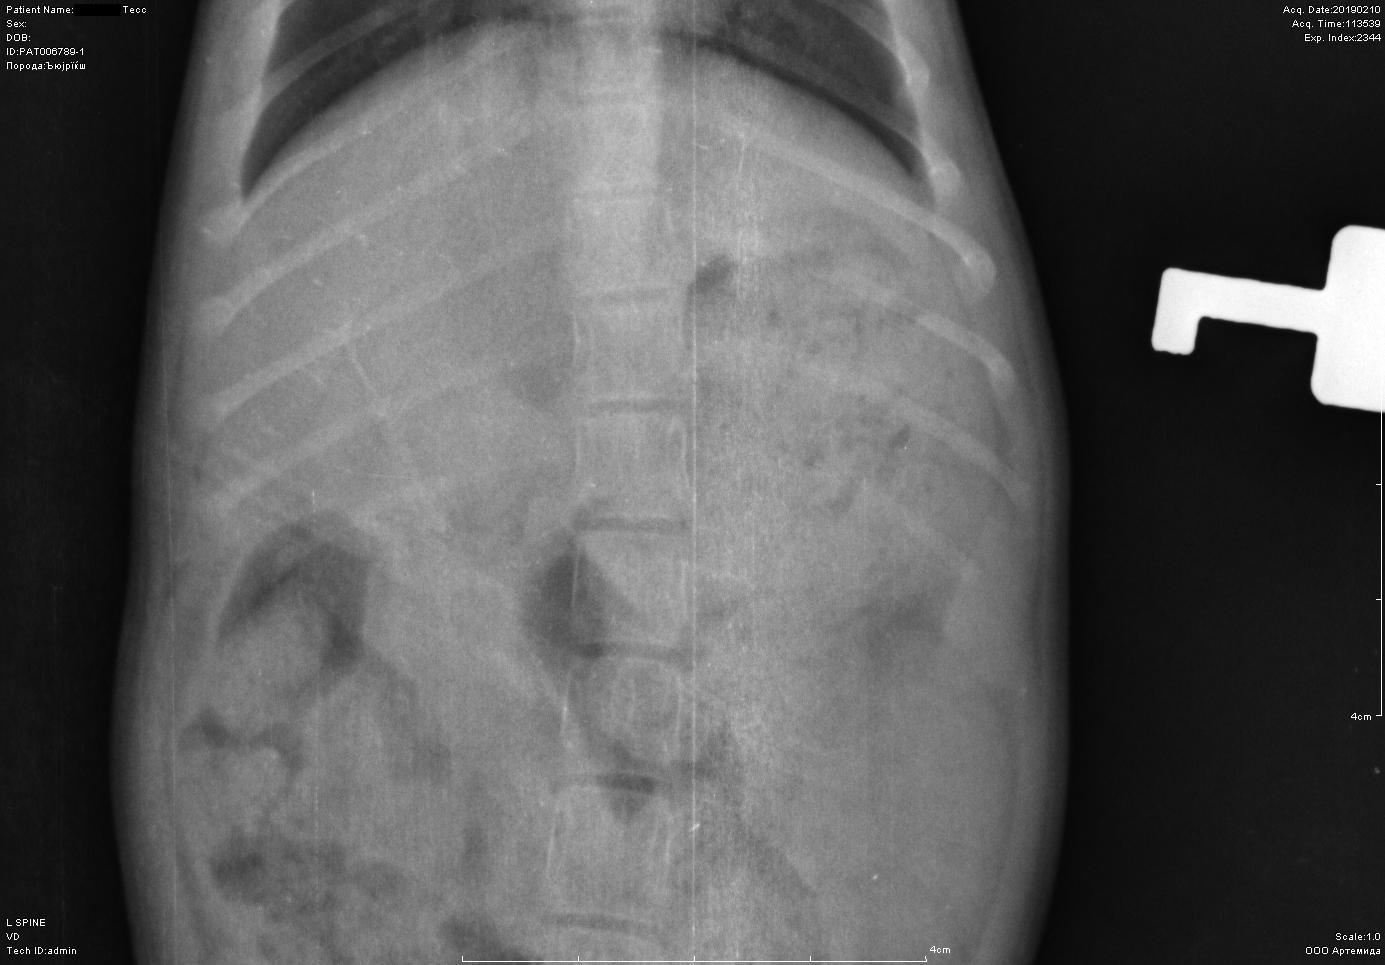

Рентген котенка

Добрый день. Котенок рожден 5 ноября 2018 года, девочка, не привита. Проглистована. Неожиданно в один момент стала припадать на задние ноги. Как бы бережет их и старается не прыгать лишний раз. Свозили два дня назад к ветеринару - всю её прощупал, говорит переломов нет, вывихов тоже. Сделали блокаду ближе в крестцу новокаина, чтобы снять симптомы. Прописал кальций в таблетках Ексел. Сейчас всё примерно так же - лапки задние бережет, но стала по активнее. Прошу специалистов, если такие тут бывают, оценить снимки, т.к. врач ещё кое-что сказал и хотелось бы услышать ваше мнение. Скан расшифровки и д/з потом приложу.

Боковая проекция